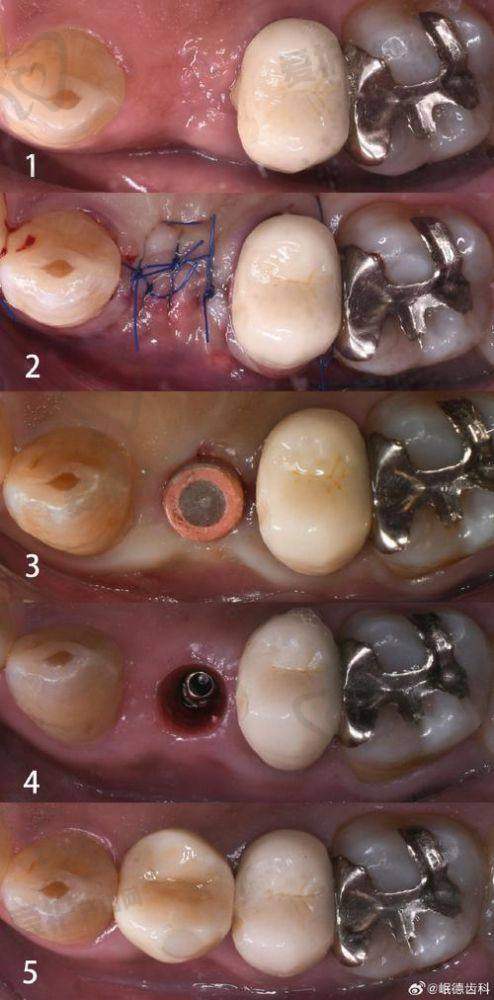

为了让大家更好地了解重庆团圆口腔医院李志锋医生开展的以色列种植牙项目,下面为大家分享一个患者实例。张先生是一位50多岁的患者,由于长期的牙齿缺失,导致咀嚼功能下降,面部也出现了一定程度的凹陷。他在朋友的推荐下来到了重庆团圆口腔医院。

李志锋医生为张先生进行了详细的检查后,建议他进行以色列种植牙手术。在与张先生充分沟通后,制定了适合他的种植方案。手术过程非常顺利,张先生在术后修复得也特别快。现在,张先生已经成功戴上了种植牙,他的咀嚼功能得到了明显改善,面部也修复了饱满。张先生对种植成效非常满意,他说:“没想到种植牙能让我的生活发生这么大的改变,感谢重庆团圆口腔医院和李志锋医生。”